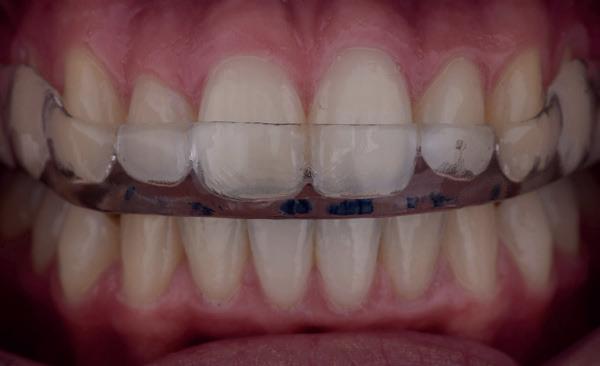

Resultaat: Na vier behandeling ervaart meneer al 50% verbetering van klachten. Hij gaat een bitje dragen voor de nacht om de druk op de tanden en kiezen beter te verdelen en schade aan het gebit te voorkomen.

Toekomstige AI-ondersteunde software zal vermoedelijk nog beter risico’s voorspellen op basis van slijtagepatronen, speekselanalyse en leefstijlfactoren. Echter, wanneer er geen scanner in de praktijk beschikbaar is dan is een handige tool het vragen of iemand elke periodieke afspraak zijn retainer meeneemt ter controle. Ontstaan daar slijtfacetten in dan weet je dat iemand s nachts actief is en zul je over moeten gaan op een night guard zoals in het voorbeeld van afbeelding 7-10). Wanneer verwijs je door?